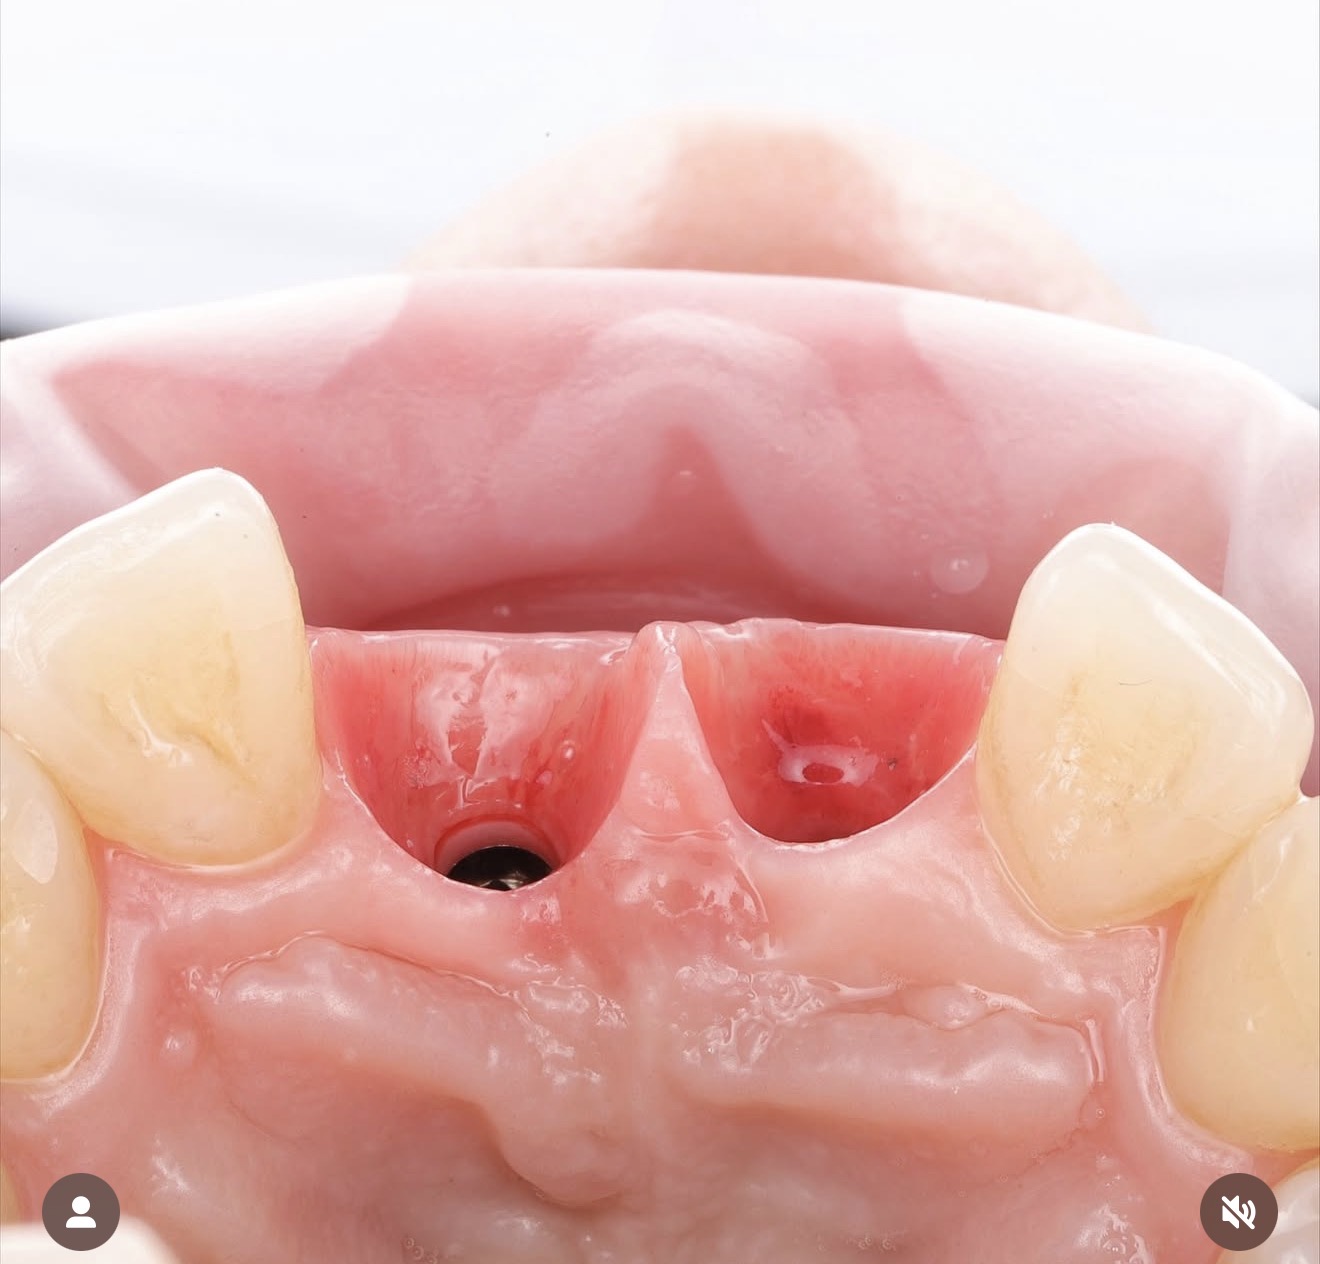

Soft tissue grafting is a set of microsurgical procedures aimed at thickening the gum and/or increasing the width of the attached keratinized tissue around a dental implant.

A sufficient amount and quality of soft tissue help protect the implant, make oral hygiene easier, and reduce the risk of peri-implantitis and gum recession.

• Before prosthetic restoration on implants or during abutment/former placement to improve soft-tissue quality.